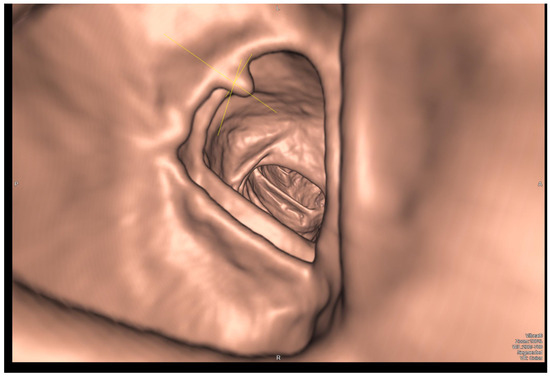

Deep Learning for Image Analysis in the Diagnosis and Management of Esophageal Cancer

Cancers 2024, 16(19), 3285; https://doi.org/10.3390/cancers16193285 - 26 Sep 2024

Esophageal cancer has a dismal prognosis and necessitates a multimodal and multidisciplinary approach from diagnosis to treatment. High-definition white-light endoscopy and histopathological confirmation remain the gold standard for the definitive diagnosis of premalignant and malignant lesions. Artificial intelligence using deep learning (DL) methods [...] Read more.

Esophageal cancer has a dismal prognosis and necessitates a multimodal and multidisciplinary approach from diagnosis to treatment. High-definition white-light endoscopy and histopathological confirmation remain the gold standard for the definitive diagnosis of premalignant and malignant lesions. Artificial intelligence using deep learning (DL) methods for image analysis constitutes a promising adjunct for the clinical endoscopist that could effectively decrease BE overdiagnosis and unnecessary surveillance, while also assisting in the timely detection of dysplastic BE and esophageal cancer. A plethora of studies published during the last five years have consistently reported highly accurate DL algorithms with comparable or superior performance compared to endoscopists. Recent efforts aim to expand DL utilization into further aspects of esophageal neoplasia management including histologic diagnosis, segmentation of gross tumor volume, pretreatment prediction and post-treatment evaluation of patient response to systemic therapy and operative guidance during minimally invasive esophagectomy. Our manuscript serves as an introduction to the growing literature of DL applications for image analysis in the management of esophageal neoplasia, concisely presenting all currently published studies. We also aim to guide the clinician across basic functional principles, evaluation metrics and limitations of DL for image recognition to facilitate the comprehension and critical evaluation of the presented studies. Full article